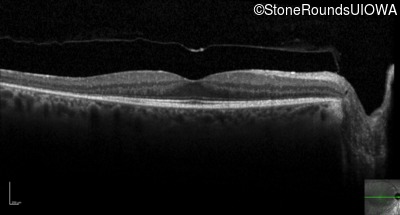

Optical Coherence Tomography - Right - 20/25 -3

Exemplar / OCT Stack

Optical Coherence Tomography - Left - 20/25 +1

Optical Coherence Tomography - Right - 20/20

Optical Coherence Tomography - Left - 20/20